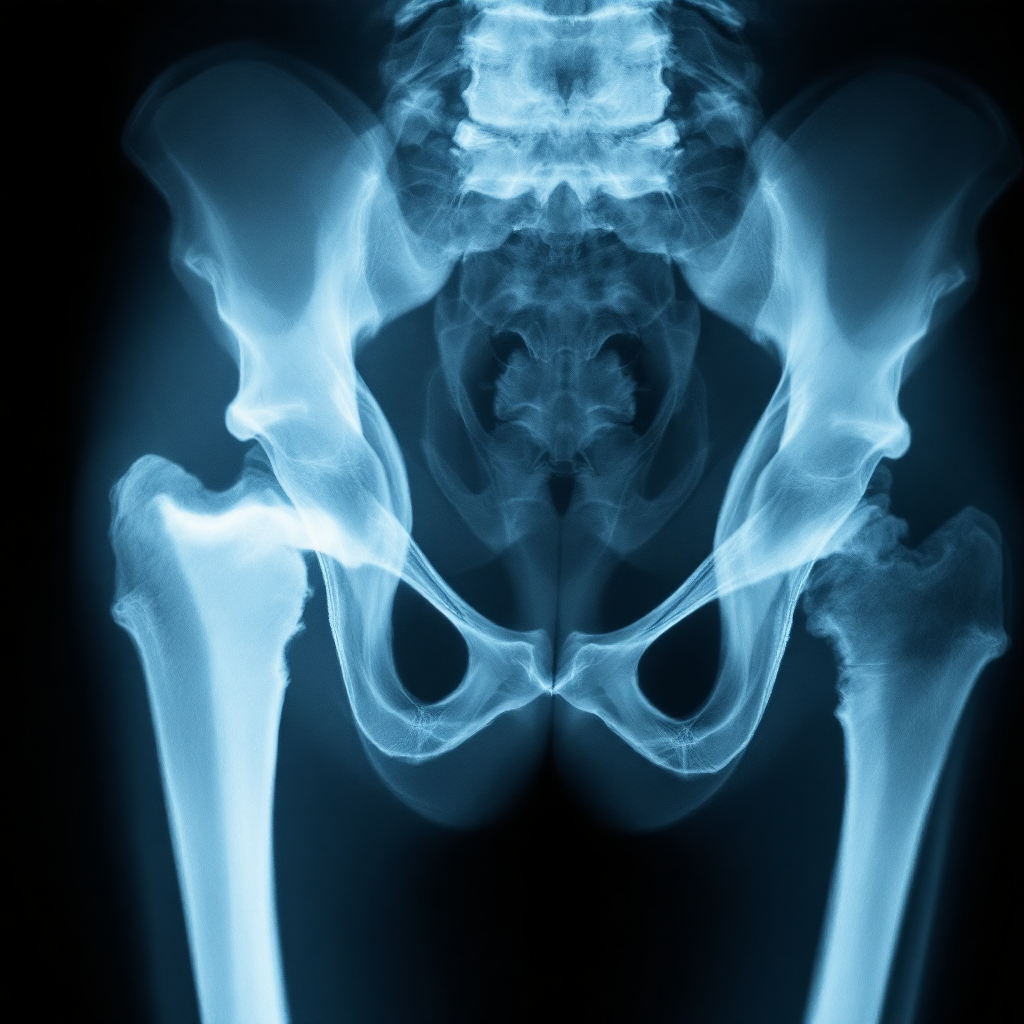

노인 고관절 골절의 심각성 🦴

고관절은 우리 몸에서 허벅지 뼈와 골반이 만나는 부분이에요. 이 부위에 골절이 생기면 단순한 통증을 넘어서 삶의 질을 급격히 떨어뜨릴 수 있어요. 특히 노인의 경우 회복 속도가 매우 느리기 때문에 더욱 치명적이죠.

통계에 따르면 고관절 골절을 경험한 노인의 20%가 1년 이내에 사망하고, 절반 이상이 독립적인 생활을 하지 못하게 된다고 해요. 이는 단지 뼈가 부러졌다는 의미를 넘어서, 생존과 직결된 문제라는 걸 의미하죠.

고관절 골절의 주된 원인은 ‘낙상’이에요. 집 안에서 일어난 작은 실수 하나로 골절이 발생할 수 있고, 그로 인해 병원 신세를 지게 되는 경우가 너무 많아요. 특히 야간 화장실 이용 시 많이 발생하죠.

고령자는 균형 감각이 떨어지고, 뼈의 밀도가 낮기 때문에 가벼운 충격에도 쉽게 부러질 수 있어요. 그래서 조기 예방이 정말 중요해요. 가정 환경부터 생활 습관까지 꼼꼼히 살펴야 해요.